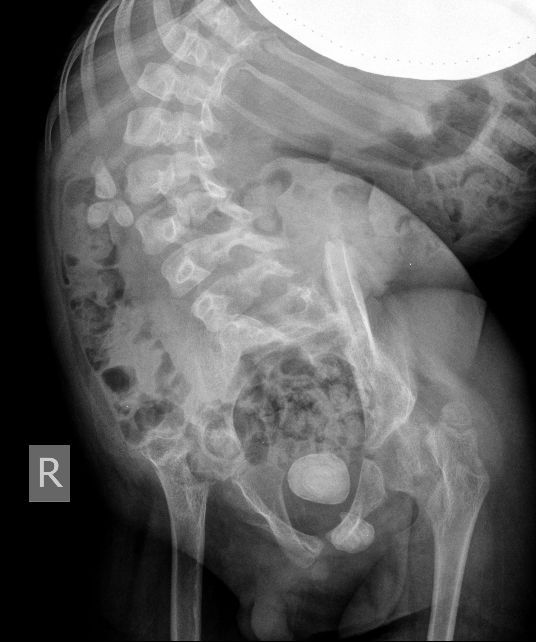

Поскольку откликов нет, добавляю экскреторные урограммы этого же пациента

DX0001.jpg

DX0002.jpg

DX0003.jpg

DX0004.jpg

DX0005.jpg

Нейрогенный мочевой пузырь (?), МКБ, конкремент мочевого пузыря, двухсторонний мегауретер, конкремент правой почки.